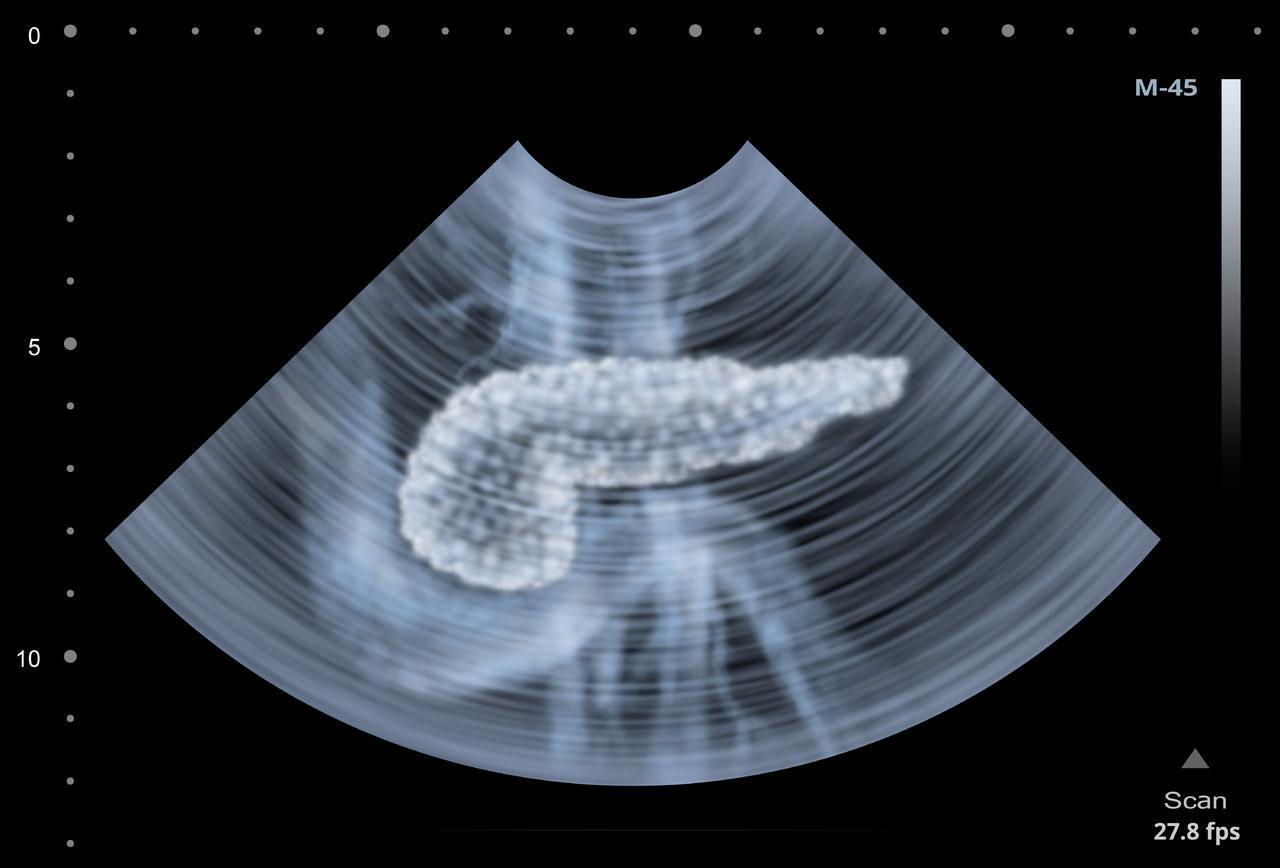

超聲胃鏡是經胃鏡導入超聲探頭,可以近距離對胰腺進行探查,多用於影像學檢查高度懷疑胰腺癌者。超聲胃鏡的陰性預測值接近100%,說明超聲內鏡陰性患者可以基本排除胰腺癌的診斷。